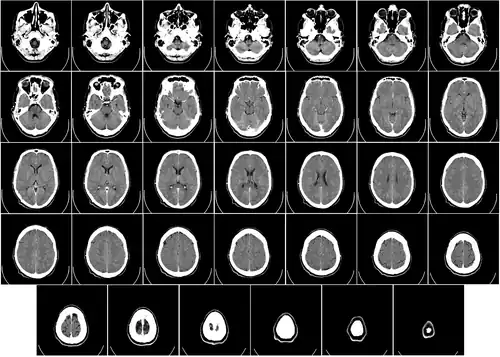

Imagen estructural y funcional

Hay varios métodos para detectar los cambios de actividad cerebral mediante imágenes tridimensionales de los cambios locales en el flujo sanguíneo cerebral. Los antiguos métodos son la SPECT y la PET, que dependen de la inyección de marcadores radiactivos en el torrente sanguíneo.

La imagen por resonancia magnética funcional (IRMf), tiene considerablemente mejor resolución espacial y no implica ninguna radiactividad.[25] La IRMf puede localizar los cambios de actividad cerebral en regiones tan pequeñas como 1 mm³ (milímetro cúbico).

El inconveniente es que la resolución temporal es pobre: cuando aumenta la actividad cerebral, el flujo sanguíneo responde con un retraso de 1 a 5 s (segundos) y tiene una duración de al menos 10 s. Por lo tanto, la IRMf es una herramienta muy útil para saber cuales regiones del cerebro están involucradas en una determinada conducta, pero da poca información sobre la dinámica temporal de sus respuestas. Una ventaja importante de la IRMf es que, debido a que no es invasiva, puede ser fácilmente utilizada en seres humanos.